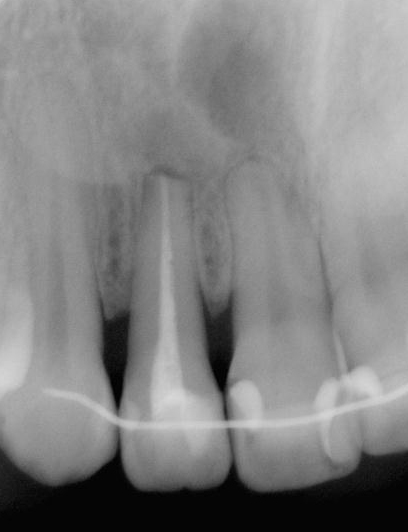

図2a 下顎中切歯の根尖病変. かなり大きいレントゲン透過像